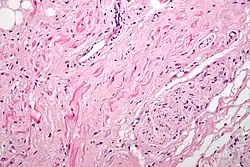

Histología

Histológicamente, el nodo sinoauricular se encuentra formado por cuatro tipos básicos de células. Las células P o pacemaker, ovoideas y pálidas, que son cardiomiocitos de despolarización.

Las células T o de transición, con una forma alargada.[6]

El otro tipo son los cardiomiocitos de trabajo, típicos de la pared auricular.

Otro tipo celular que siempre se encuentra son los fibrocitos.

Existen neuronas, las células de Purkinje, que están en íntima relación con fibras del sistema nervioso autónomo.